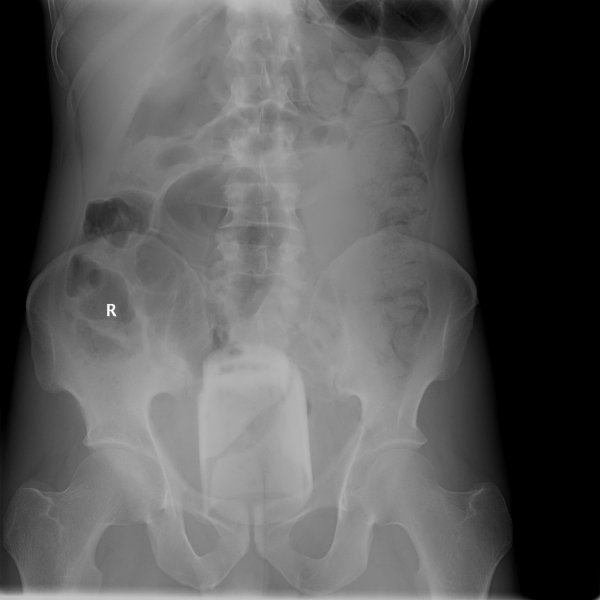

Специалисты по рентгеновской диагностике регулярно сталкиваются с посторонними предметами внутри тела человека. Обычно лишние предметы попадают в пищеварительную систему из-за неосторожности при еде или во время неудачных любовных игр. Почти всё удается вытащить — с хирургическим вмешательством или без него. выбрал самые необычные находки радиологов, которыми они делились на сайте Radiopaedia.org.